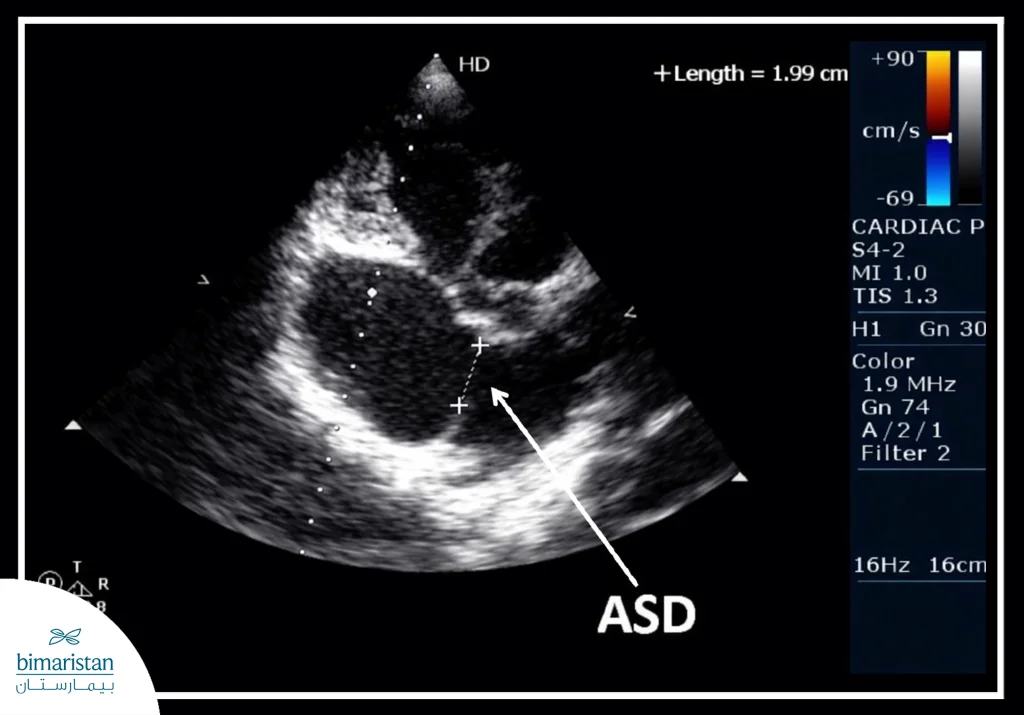

- Echocardiography: It shows the chambers and valves of the heart, assesses blood flow within the heart, and detects abnormal shunting between the atria.

- Transthoracic echocardiography (TTE): Used to evaluate the effect of the defect on the heart and lungs, including left-to-right atrial shunting.

- Transesophageal echocardiography (TEE): Helps to more accurately determine the size, shape, and location of the defect, as well as evaluate the heart valves.